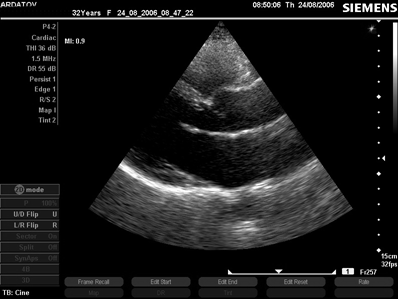

Дополнительными свидетельствами в пользу ПМК служит избыточная длина передней створки МК, изогнутость задней, продолжающееся систолическое движение передней створки в сторону левого предсердия, поздняя систолическая или эксцентрическая митральная регургитация, пролапс трикуспидального клапана, расширение синусов Вальсальвы и пролапс аортального клапана. Утолщение и деформация створок в наибольшей степени проявляется на кончиках створок, те становятся похожи на булавочные головки. Иногда утолщение распространяется и на хорды. В предельных случаях трудно различить миксоматозную дегенерацию и массивные вегетации на МК (рис. 8).

Рис. 8. Последовательная серия эхограмм митрального клапана с признаками миксоматозной дегенерации, пролапсом передней створки и систолическим расхождением створок (собственное наблюдение).

Чем сильнее деформирован клапан, тем выше шансы выявить локальное утолщение эндокарда межжелудочковой перегородки в месте их соприкосновения. В клиническом плане увеличивается вероятность жалоб и осложнений (боли в грудной клетке, аритмии, инфекционный эндокардит, эмболии, разрыв хорд).